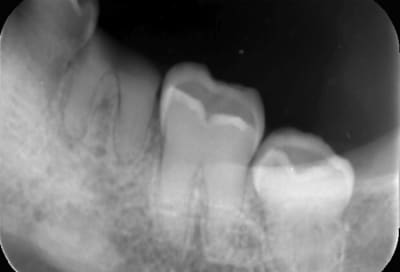

Radio 26

D9f30056 befd 4a58 a9d3 44fed132d3d4 zi8p3v - Eugenol